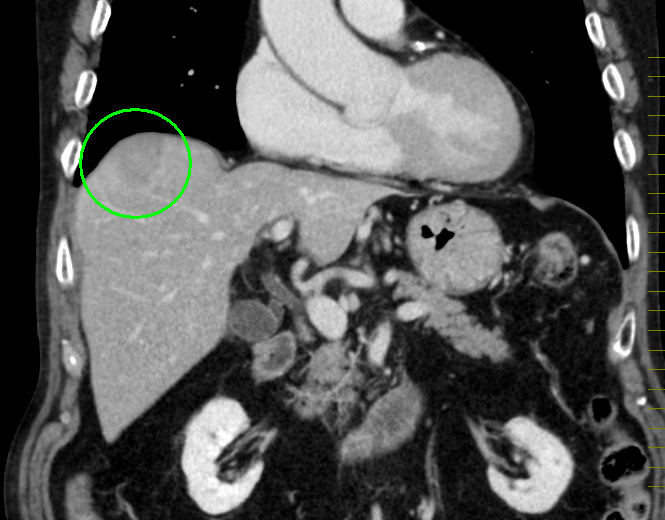

肝臓がんの検査としては、まず血液検査(肝機能検査、腫瘍マーカー検査)と超音波(エコー)検査を行います。必要により、CT検査もしくはMRI検査による画像検査も組み合わせて実施します。画像検査で良性/悪性の鑑別が難しい場合は、直接腫瘍組織を採取して調べる検査(針生検)を追加する場合もあります。

CT画像